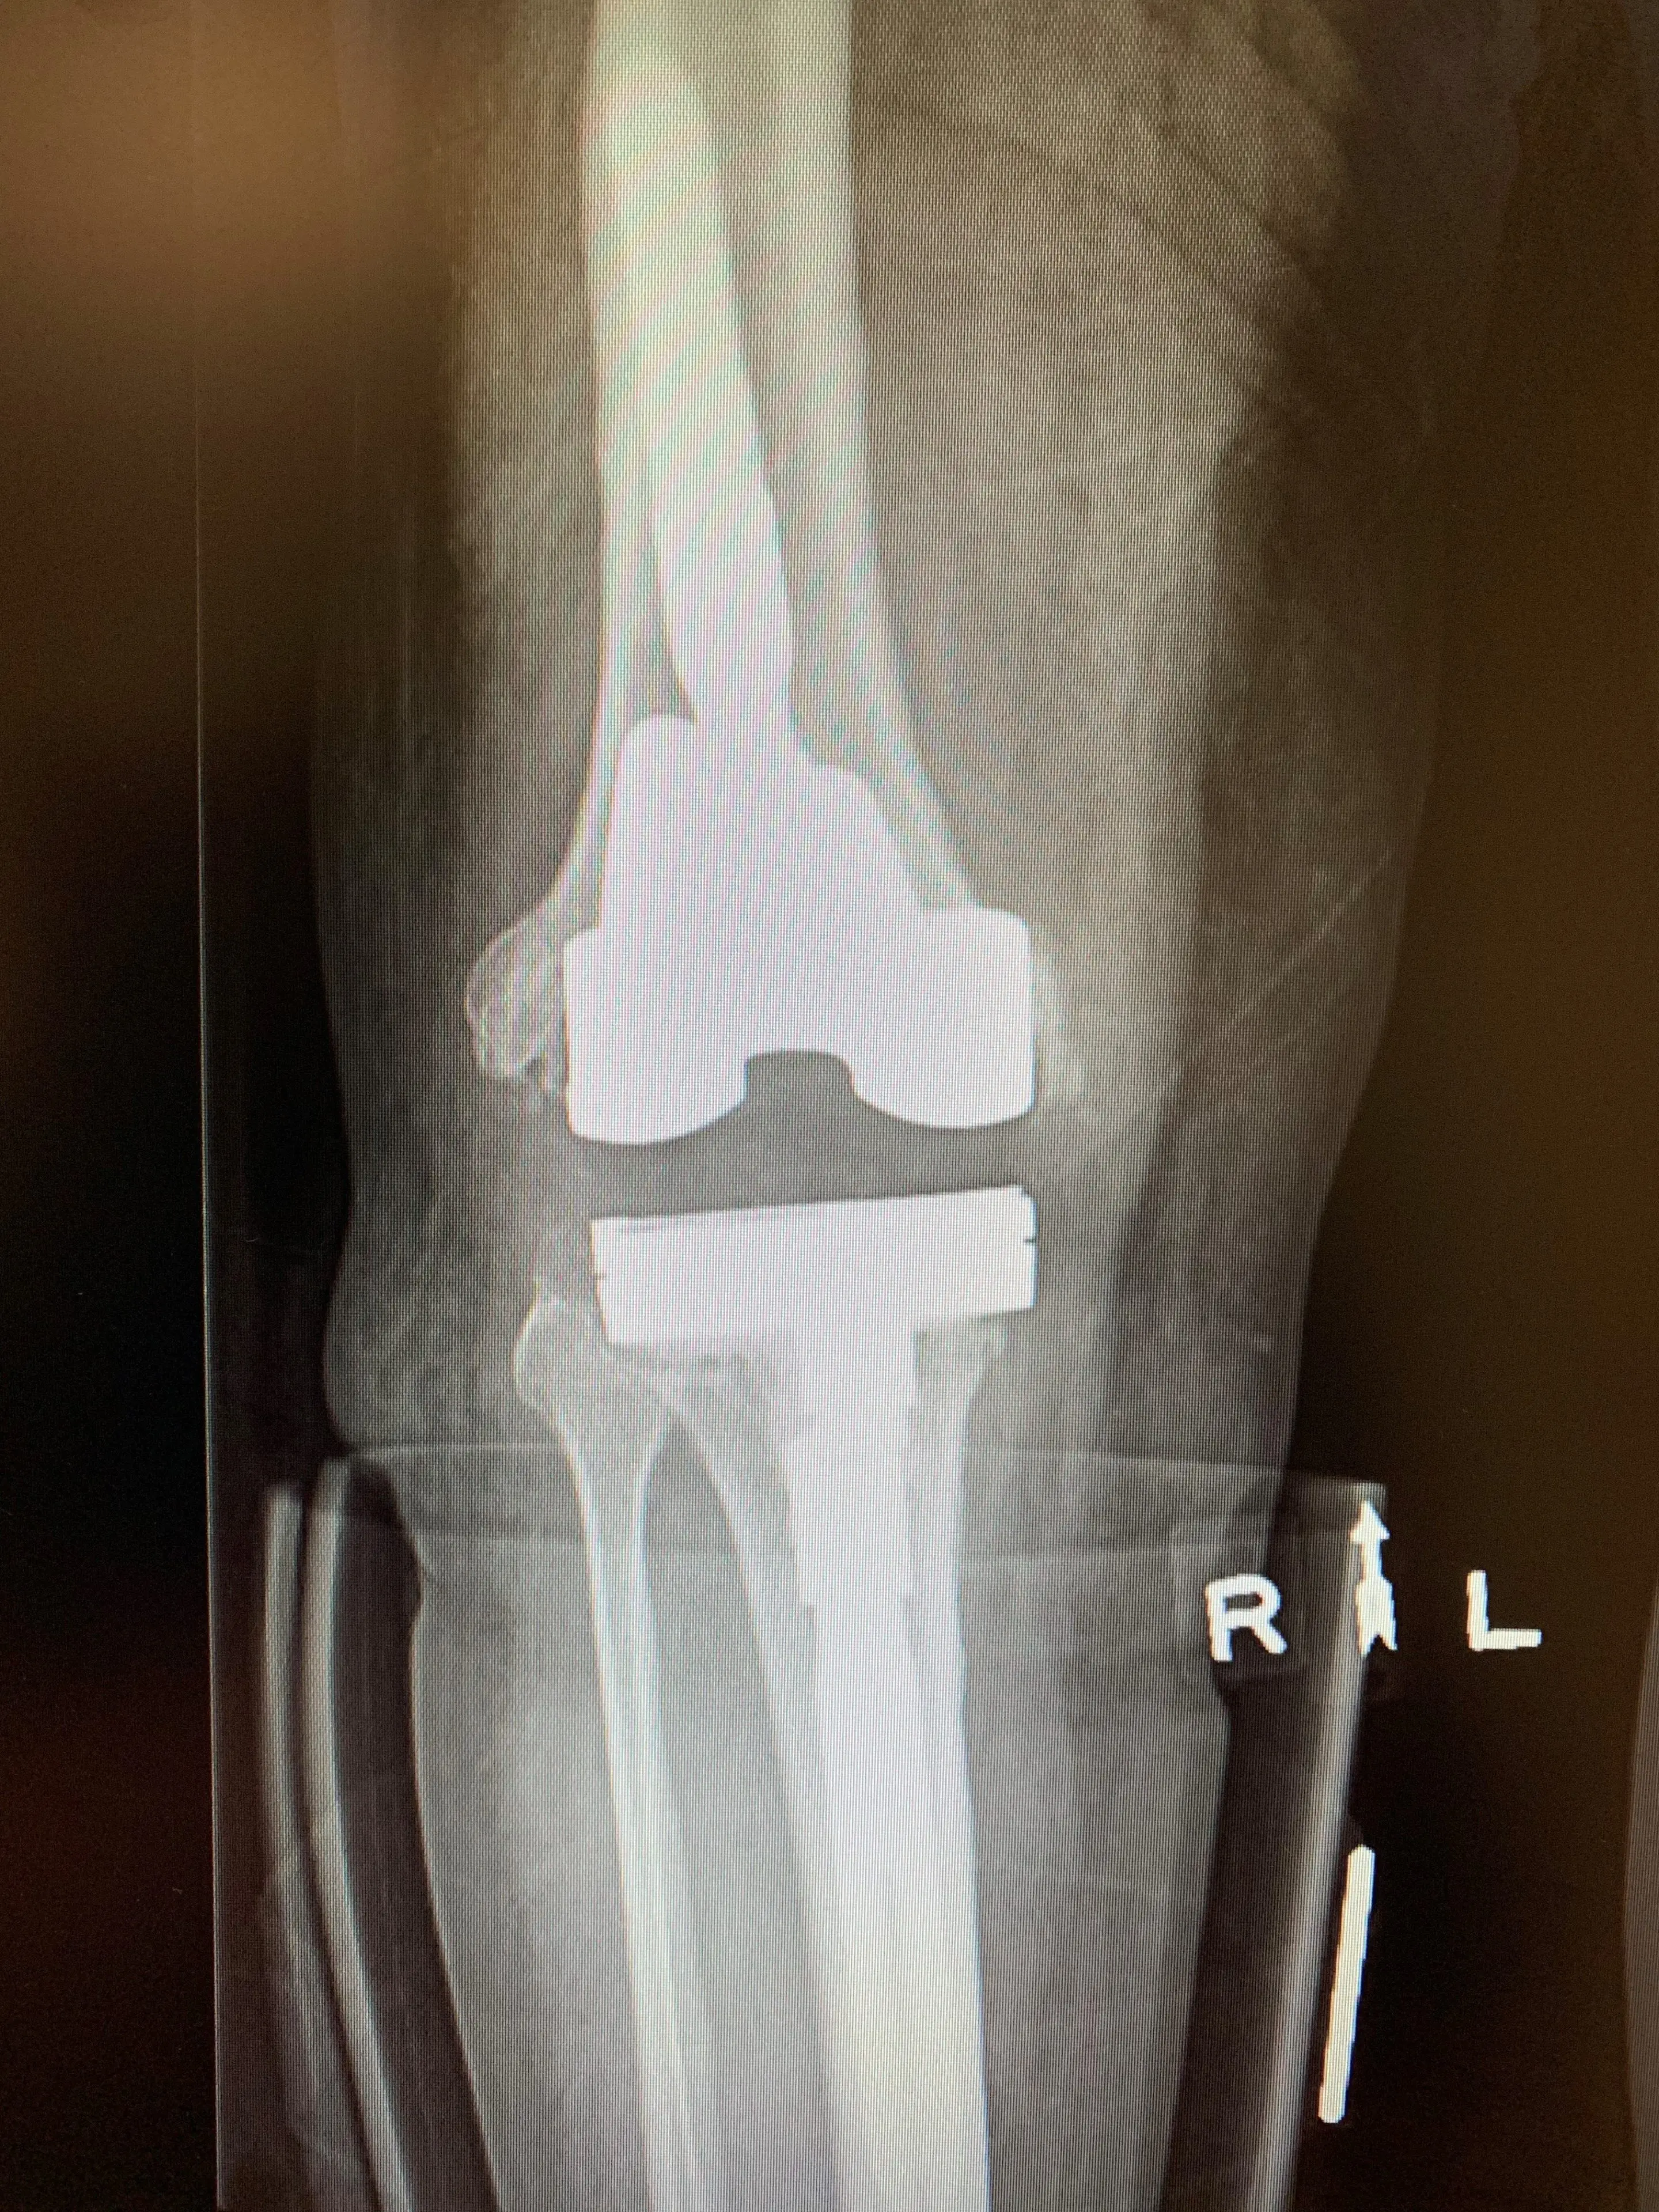

He consented to this, and we performed the 1st stage of his revision within 3 weeks of his diagnosis. We removed all the prosthetic components and replaced these with articulating spacer components, constructed entirely of antibiotic-laiden cement. These will be allowed to elute their antibiotics locally, along with systemic antiobiotic therapy until the infection is deemed to be eradicated – indicated by decreasing serum inflammatory marker levels.

Post-opTreatment of infected knee replacement. A staged reconstruction in a 64 year old maleb

Treatment of infected knee replacement. A staged reconstruction in a 64-year-old male.